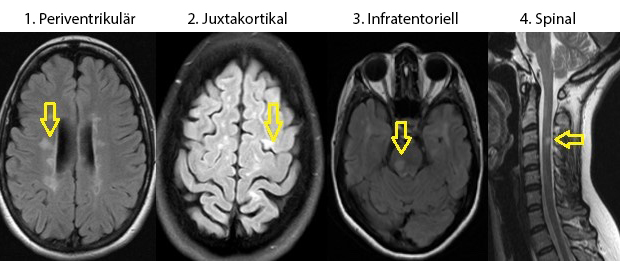

- Befund: multilokuläre Läsionen

- Typische Lokalisationen:

- Periventrikuläres Marklager, insb. im Balken

- Juxtakortikal/kortikal (hilfreich zur Differenzierung von vaskulären Läsionen)

- Infratentoriell, insb. im Pons

- Intraspinal: meist zervikal, gelegentlich thorakal; typischerweise monosegmental

“Diseminacion en espacio.jpg” von DraazucenaDL https://commons.wikimedia.org/wiki/File:Diseminacion_en_espacio.jpg, CC BY-SA 4.0 https://creativecommons.org/licenses/by-sa/4.0 via Wikimedia Commons. Die Beschriftungen wurden übersetzt und entsprechend ausgetauscht.